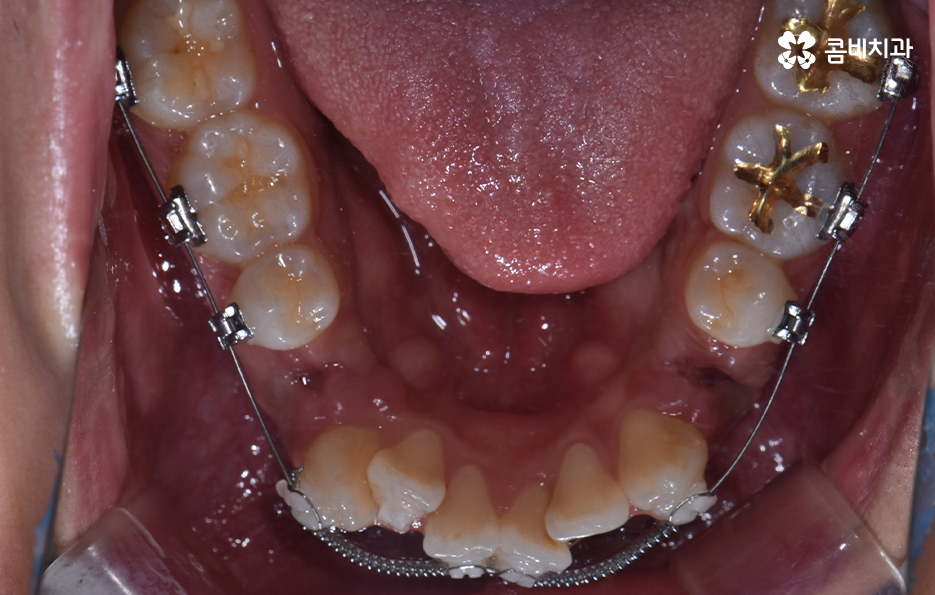

치아교정을 위한 발치교정 과정은 대부분 소구치 라고 불리는 첫번째 작은 어금니를 발치하게 되며 좌우, 위 아래 총 4개의 소구치를 발치한 후에 덧니가 재배열 될 수 있는 공간을 만들기 위하여 우선 송곳니를 후방으로 이동시키고 있어요

그 다음으로는 송곳니가 후방으로 이동하면서 확보된 공간으로 앞니의 배열을 가지런하게 맞추고 있는데요. 앞니의 재배열과 함께 발치 교정으로 인해 빈 공간이 발생한 부분을 없애고 전체적인 치열을 미세하게 조절하게 되는데 발치교정은 치아의 움직임이 많은 편이기 때문에 교합이 잘 맞도록 마무리 배열을 잘해야 하며 그와 함께 치아가 많이 움직이는 만큼 얼굴형의 변화와 입술라인 등의 변화가 클 수 있다는 점에서 치료 후 결과를 잘 예측하여 처음 치료 계획부터 마무리까지 섬세하게 진행하실 필요가 있어요